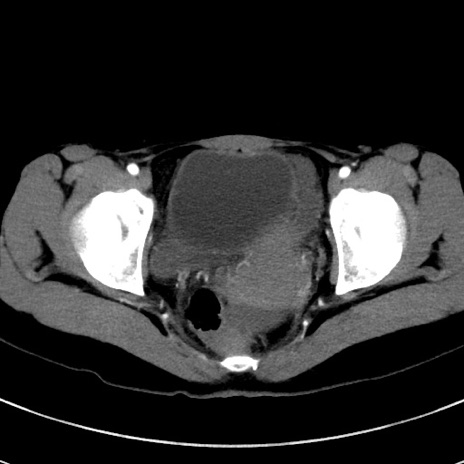

症例17(横断像)

【症例】20歳代女性

【主訴】嘔吐、下腹部痛

【現病歴】昨日夕食後に嘔吐し下腹部痛が出現。本日になっても嘔吐持続し改善しないため来院。

【身体所見】意識清明、BT 37.2℃、BP 108/67mmHg、腹部:平坦、やや硬、下腹部正中から右にかけて圧痛あり、反跳痛軽度あり、tapping pain(+)。

【データ】WBC 13600、CRP 14.94